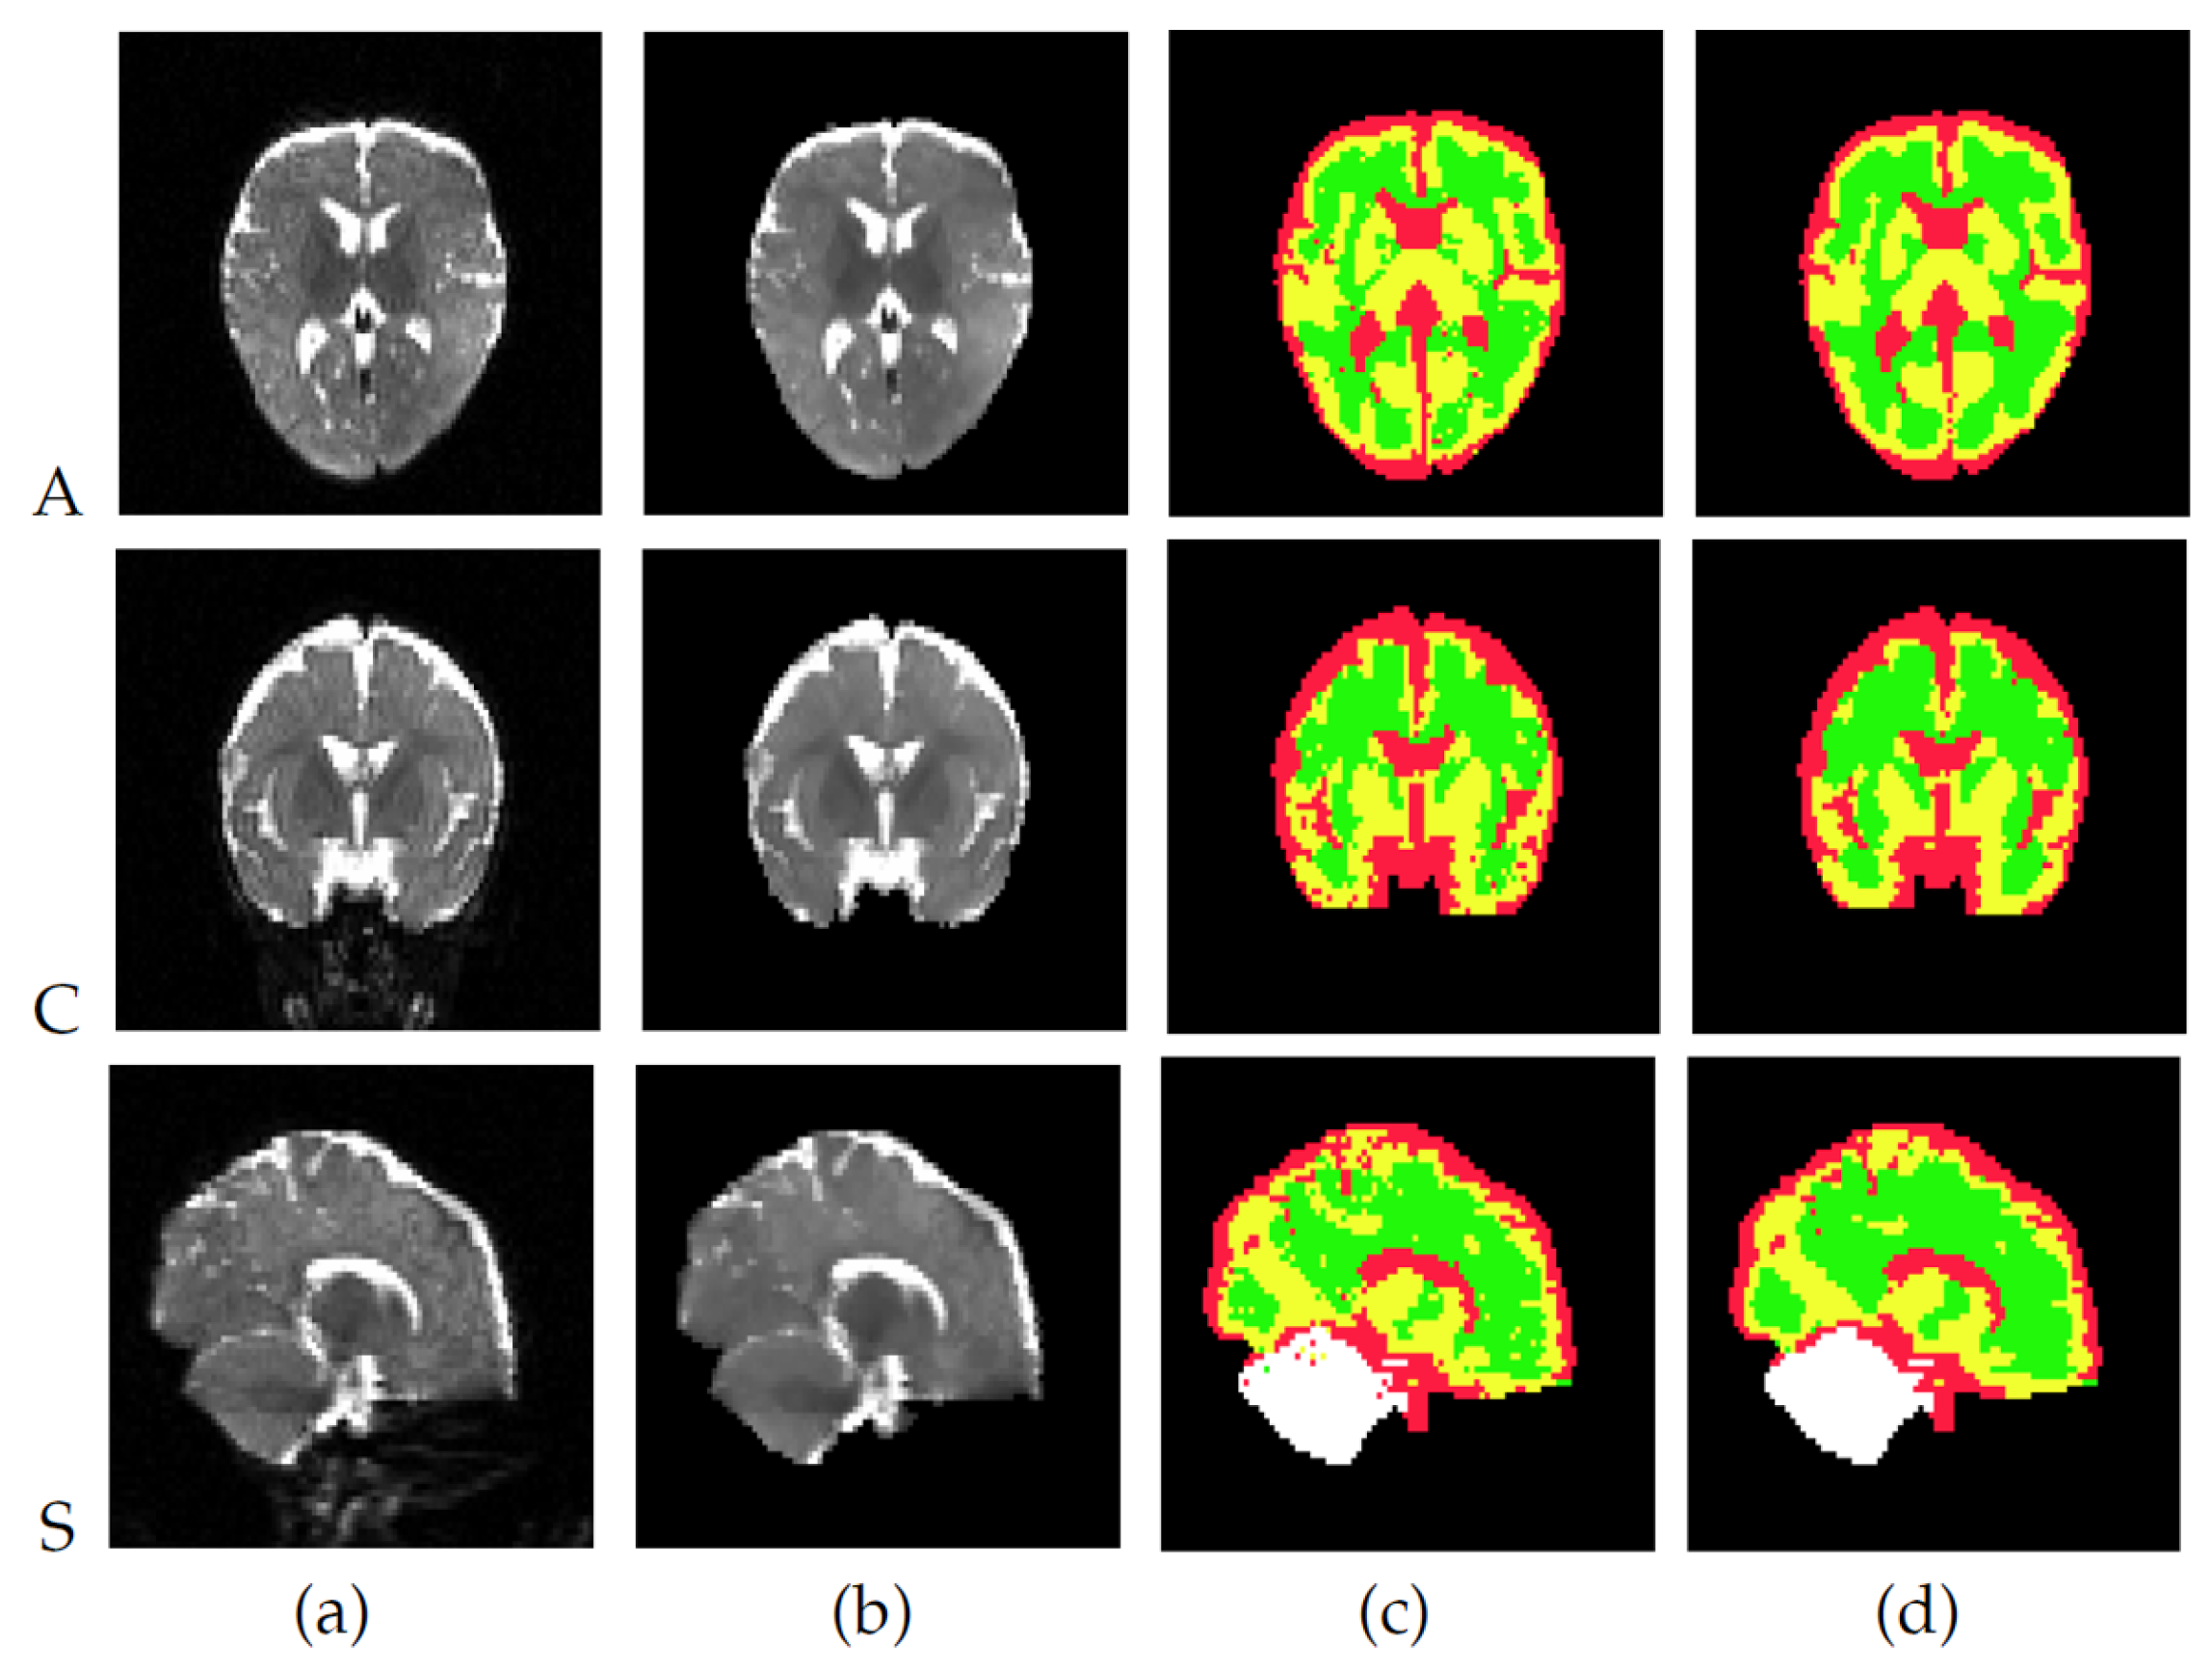

Segmentation Results